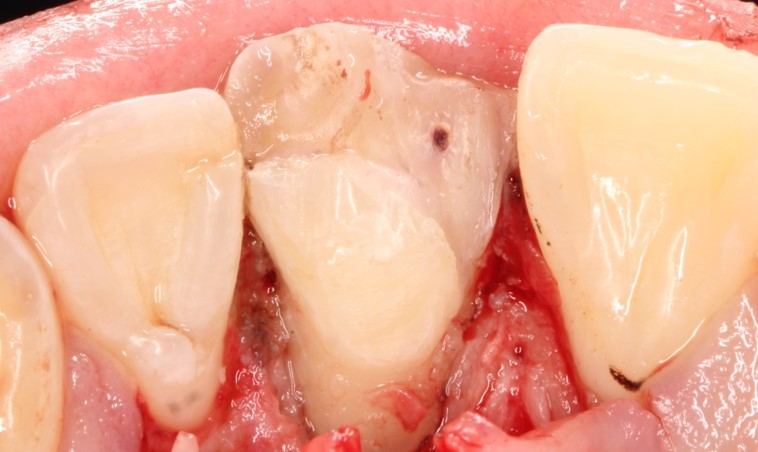

После фиксации отломка были убраны излишки жидкотекучего композита

Далее была восстановлена медиальная стенка зуба до ушивания десны.